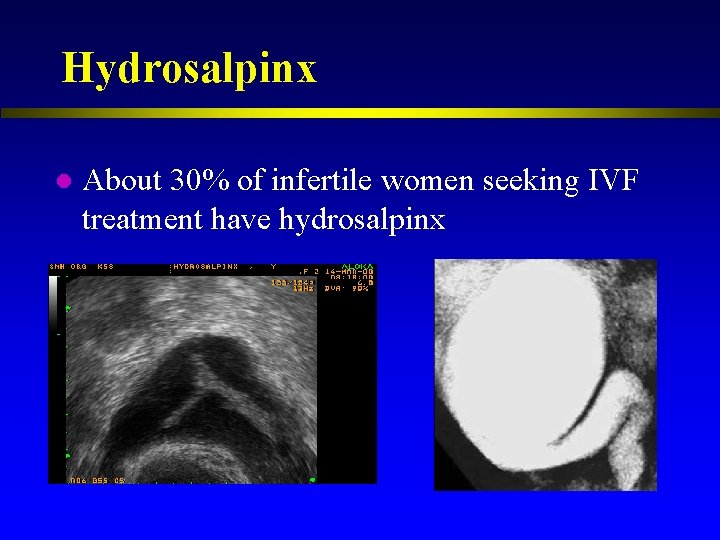

Hydrosalpinx l About 30% of infertile women seeking IVF treatment have hydrosalpinx